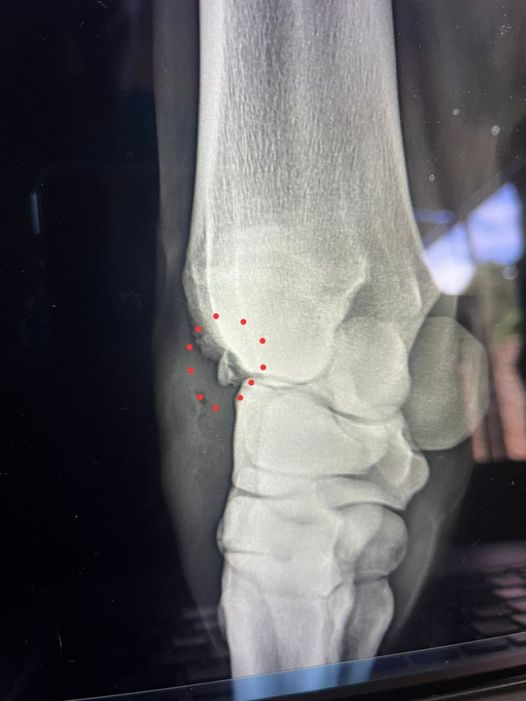

«TIME TRAVELER no podrá alcanzar la codiciada Triple Corona. Luego de su magnífico triunfo en el clásico Cría Nacional GI, donde demostró gran coraje y calidad para no dejarse pasar, un estudio radiológico reveló que sufrió una pequeña fractura en su carpo izquierdo; un ‘chip’ que requiere cirugía para extraerlo y un prudencial tiempo de reposo. En un lapso de 43 días, ganó 3 carreras entre los 1300 y 2000 metros, lo que evidencia su gran calidad».